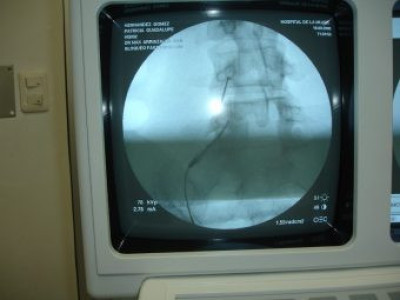

Colocacion de agujas para bloquear facetario con radiofrecuencia

Envíado por Dr. Maximiliano Eduardo Arriaza Asturias